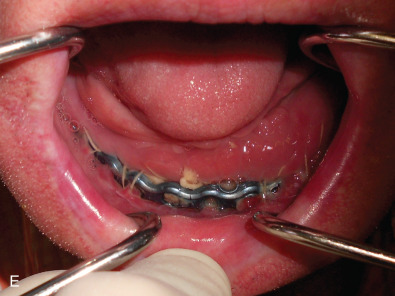

All of these systems allowed for convalescent function – life without MMF. RIF had the potential of dramatically shortening the course of treatment. However, its use was highly technique-sensitive with a steep learning curve. Thus, the incidence of complications increased dramatically due to operator error. Complications related to inadequate reduction – “the OIF” (open internal fixation … without the reduction) ( Figs. 1.16.1–1.16.3 ), inadequate fixation ( Figs. 1.16.4–1.16.7 ) and surgical misadventure ( Fig. 1.16.8 ) began to appear. Indeed, by the early 1990s operator error was the number one cause of mandibular fracture complications. Quite obviously, RIF is very unforgiving. When done poorly, one has a rigidly fixed mistake. The latest series of misadventures are related to the use of IMF screws. Bone-anchored arch bars will most likely be next. Not all believe that RIF and convalescent function is cost-effective with respect to the increased cost, potential for complications, and patient acceptance.